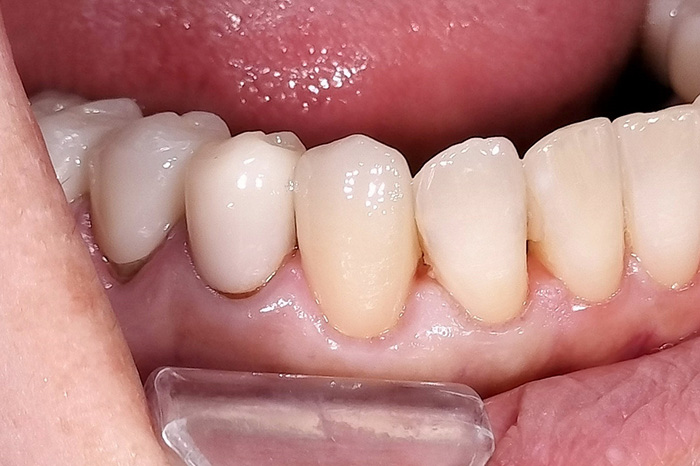

奥歯の噛み合わせと前歯の歯並びを同時に改善した症例(インビザライン+ジルコニア)

患者様は、奥歯でしっかり噛めないことと、前歯の歯並びの乱れを気にされ来院されました。診査の結果、前歯部の叢生(歯並びの乱れ)と、臼歯部の離開咬合(奥歯がしっかり噛み合っていない状態)が認められました。また、臼歯部には古い金属修復物が装着されており、機能面だけでなく審美面においても改善が必要な状態でした。

【治療後】

前歯の歯並びが整い、見た目の改善が認められました。また、奥歯でしっかり噛める状態となり、咬合機能の回復が得られています。

本症例では、歯並びの改善だけでなく、噛み合わせの回復と審美性の向上を同時に行っています。当院は一般歯科と矯正治療の両方に対応しているため、矯正治療後に別の医療機関で補綴治療を行う必要がなく、一貫した治療計画のもとで治療を完結することが可能です。また、奥歯の噛み合わせを矯正治療のみで改善する場合、治療期間が長くなることがありますが、本症例では補綴治療(アンレー)を併用することで、比較的短期間で咬合の改善を行いました。さらに、古い金属修復物をジルコニアに置き換えることで、見た目の改善と機能性の両立を図っています。